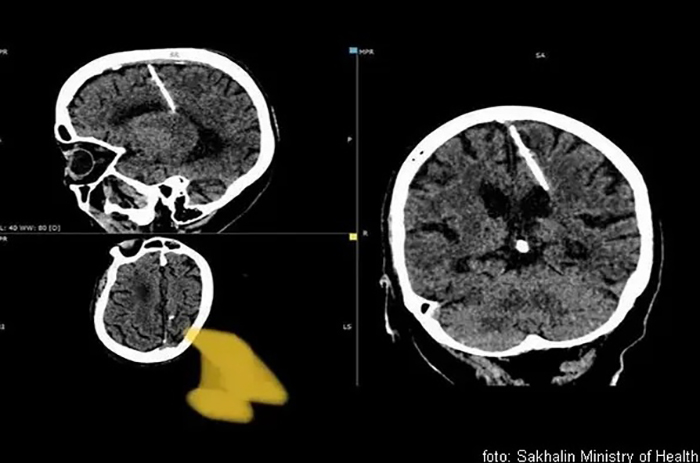

Osamdesetogodišnja žena na dalekom istoku Rusije živi sa iglom dugačkom 3 cm u mozgu od rođenja, otkriveno je prilikom skeniranja.

Lokalno zdravstveno odeljenje regiona Sahalin veruje da je žena bila žrtva neuspjelog čedomorstva tokom Drugog svjetskog rata.

“Takvi slučajevi tokom godina gladi nisu bili neuobičajeni. Njeni roditelji su vjerovatno odlučili da svoje dijete ubiju”, saopštila je lokalna zdravstvena služba. Ovaj metod se često koristio da bi se sakrili dokazi o zločinu, navedeno je u saopštenju, prenosi portal zanimljivostidana.com.